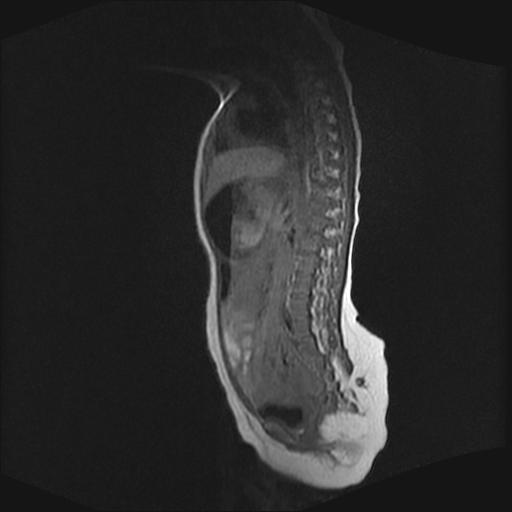

四个月的女婴,ct示脊膜膨出.

脊柱裂、脊膜膨出,请结合临床除外皮毛窦。

脂肪脊髓脊膜膨出

脊柱裂、脊膜膨出